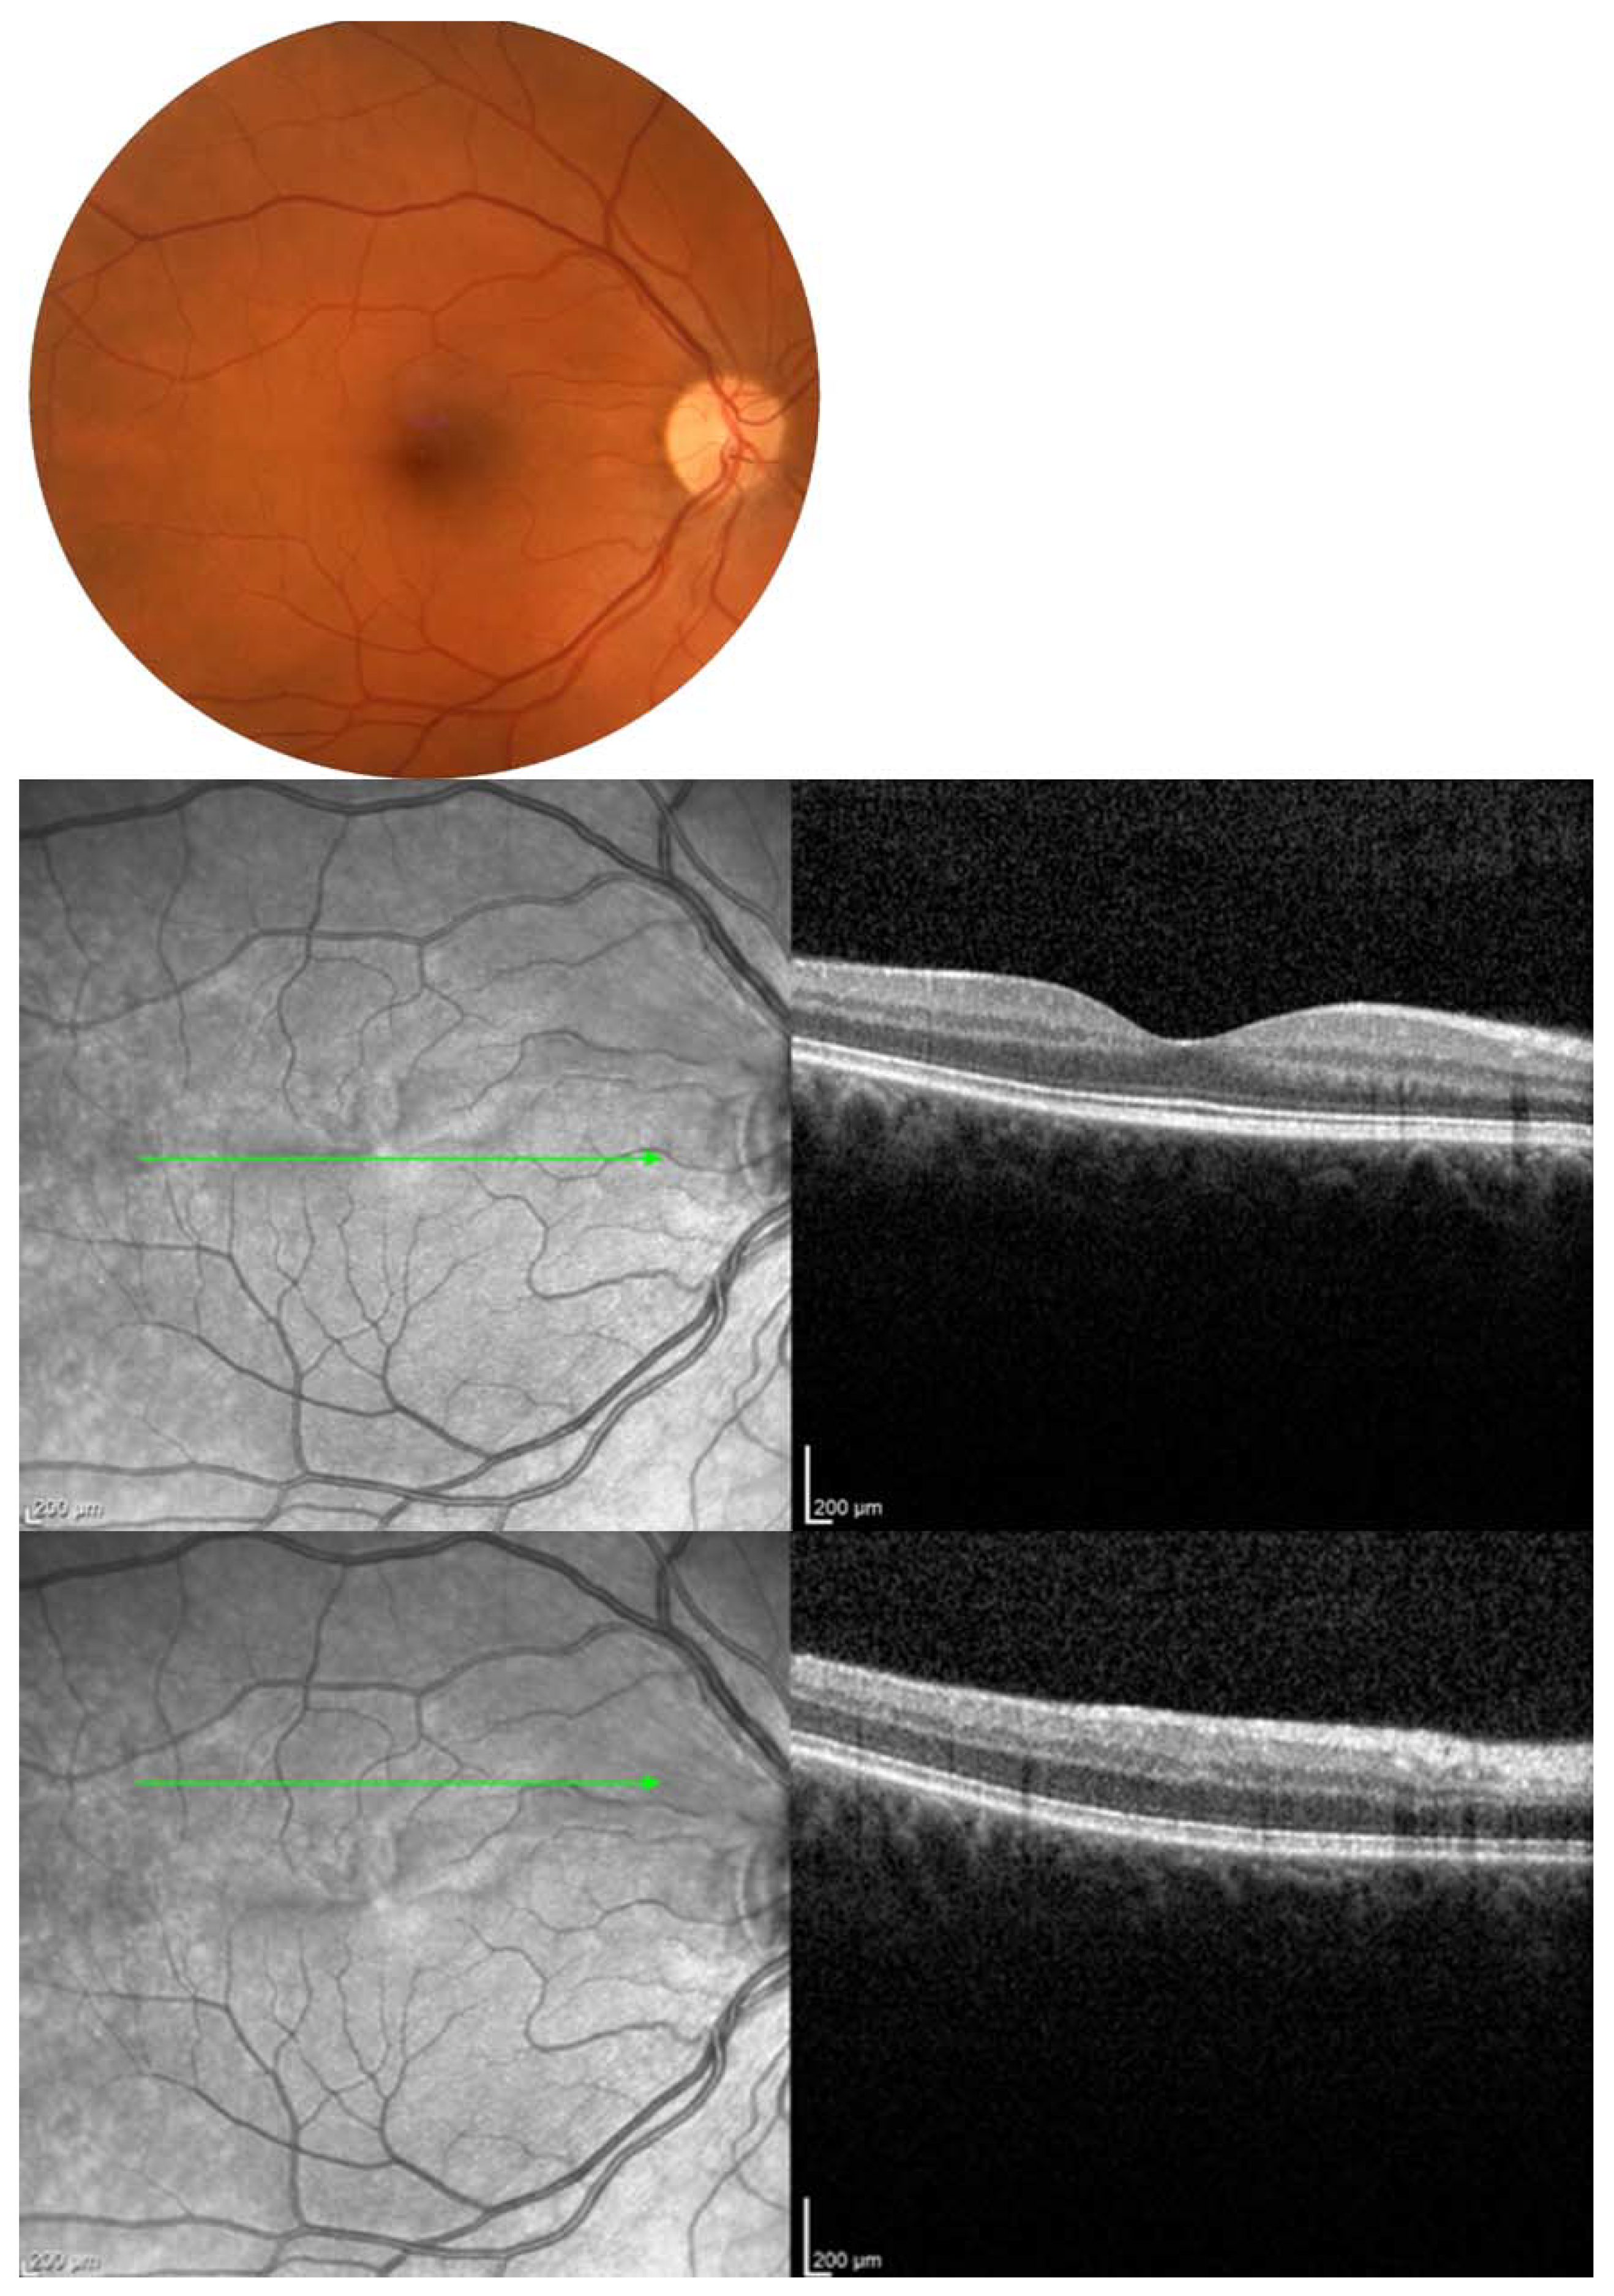

- Malerbi, F.K.; Novais, E.A.; Emmerson, B.; Bonomo, P.P.; Pereira, A.J.; Lottenberg, C.L.; Maia, A. Hyperbaric oxygen therapy for choroidal neovascularization: A pilot study. Undersea Hyperb. Med. 2015, 42, 125–131. [Google Scholar] [PubMed]